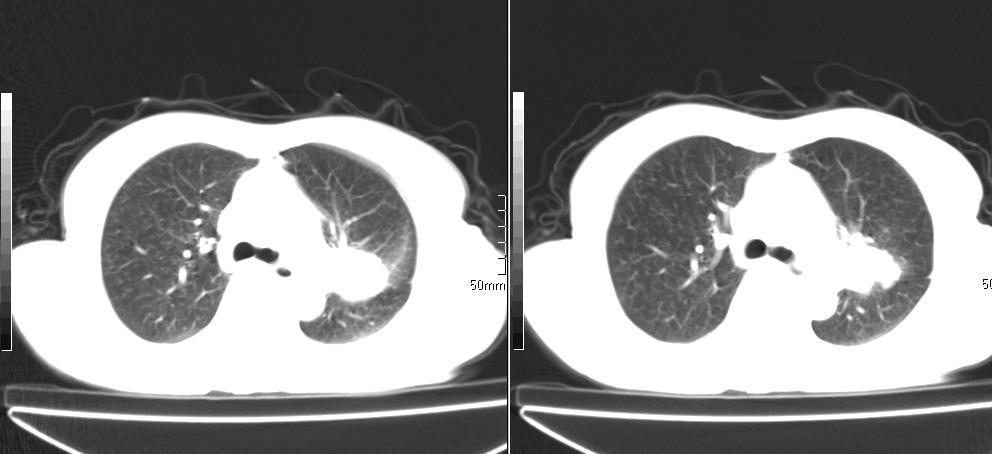

标题: CT26857:女,60岁,胃部不适前来就诊,不咳嗽,乏力,胸椎 [打印本页]

1、胸椎有骨质破坏伴周软组织,考虑胸椎转移。2、考虑左肺上叶尖后段支气管开口区周围型肺癌可能。

1、胸椎有骨质破坏伴周软组织,考虑胸椎转移。2、考虑左肺中央型肺癌可能。

椎体有高密度影,多系转移。

左肺中央型肺癌,胸椎大致正常,必要时ect扫描